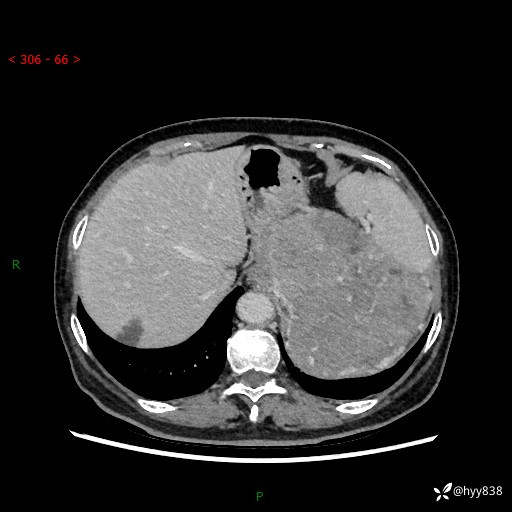

据说只有腹膜后,才能见到如此巨大的肿块---(有结果)

主诉:发现腹膜后占位1周

简要病史:患者1周前因头晕在当地第二人民医院检查发现左侧腹膜后区巨大富血供占位性病变,患者自诉腹部稍硬,无其他不适,无血尿,无腰痛等不适,患者为求进一步治疗来我院,门诊以“腹膜后占位性病变”收入我科。 起病以来,患者精神、饮食、睡眠可,大便正常,小便如上述,体力体重无明显改变。

临床诊断:腹膜后占位

腹部CT增强(动脉期+静脉期 ) ---平扫外院